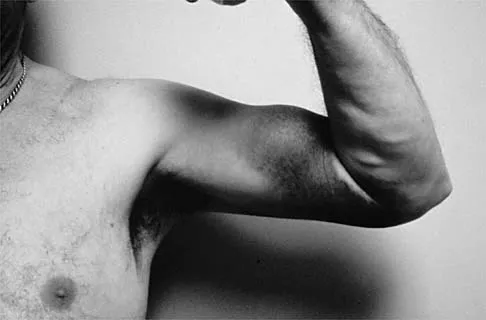

A 58-year-old man has persistent pain and weakness of his right shoulder after undergoing primary rotator cuff repair 1 year ago. A clinical photograph is shown in Figure 11. Which of the following factors might make functional improvement problematic with revision rotator cuff surgery?

Functional improvement after revision rotator cuff surgery is most likely to occur in patients with an intact deltoid, good-quality rotator cuff tissue, preoperative active elevation alone to 90 degrees, and only one prior rotator cuff repair. In this patient, the compromised deltoid origin might make functional improvement less likely. Djurasovic M, Marra G, Arroyo JS, et al: Revision rotator cuff repair: Factors influencing results. J Bone Joint Surg Am 2001;83:1849-1855. Bigliani LU, Cordasco FA, McIlveen SJ, et al: Operative treatment of failed repairs of the rotator cuff. J Bone Joint Surg Am 1992;74:1505-1515.